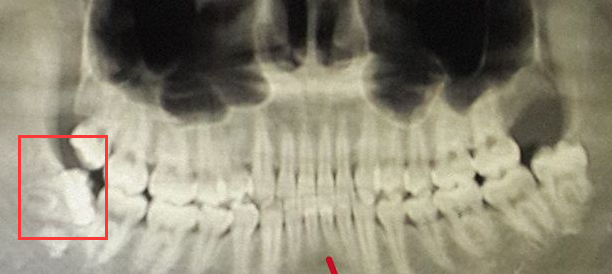

深圳口腔醫院醫生介紹到,一般情況下,牙齒矯正之前建議先把智齒拔掉,以為(wei) 智齒在口腔內(nei) 往往不是正常位置的,長歪的智齒會(hui) 占用口腔內(nei) 本來就不多的空間,拔掉智齒後一來可以騰出一些矯正需要的空間;二來,智齒保留下來,可能會(hui) 在矯正的完成後擠壓鄰牙,造成牙齒畸形反彈的情況。

所以建議根據自己的智齒情況,建議在牙齒矯正之前先拍一張口腔全景片,然後在專(zhuan) 業(ye) 醫生指導下製定合適的方案,確定是否需要拔除智齒。一般生會(hui) 提前告知大家,大家愛也可以和醫生進行溝通,讓醫生了解自身的想法,商議決(jue) 定是否需要拔牙。